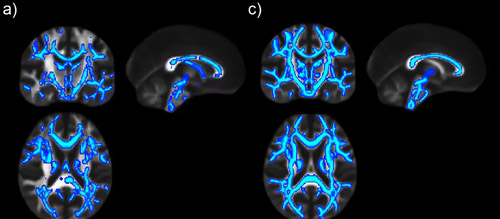

Los daños cerebrales producidos por el consumo de alcohol siguen progresando cuando cesa la ingesta, durante las primeras semanas de abstinencia, según ha demostrado un trabajo con resonancia magnética realizado conjuntamente por el Instituto de Neurociencias de Alicante (centro mixto del Consejo Superior de Investigaciones Científicas y la Universidad Miguel Hernández) y el Instituto Central de Salud Mental de Mannheim (Alemania). El estudio, publicado en la revista JAMA Psychiatry, rebate la creencia de que las alteraciones en el cerebro empiezan a normalizarse inmediatamente después de dejar el consumo de alcohol.

La investigación, cuya primera autora es la investigadora Silvia de Santis, del Instituto de Neurociencias, muestra que seis semanas después de haber dejado de beber siguen produciéndose cambios en la materia blanca del cerebro, según revela el estudio de neuroimagen realizado a más de noventa pacientes voluntarios internados en un hospital de Alemania para su tratamiento de rehabilitación.